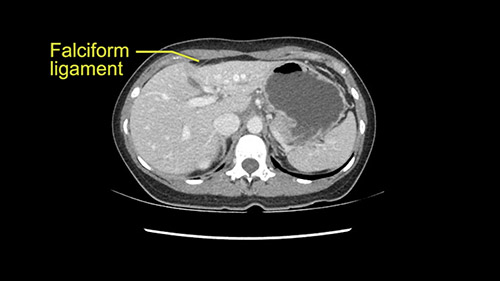

So if we look at the CT scan, on the axial, it’s a larger lesion. It’s about 6 or 7 or 8 centimeters. So it does look a bit threatening in terms of its resectability but if you really drill down deeply into the anatomy, and I think the coronal [imaging] is even better, you can see that the entire mass is on the patient’s left side of the falciform ligament. So it’s really only a left-sided tumor and not even really a left-sided tumor because Segment 4 is uninvolved anatomically.

Otherwise, the dissection at the porta is on the left side of the falciform [ligament] so we don’t worry too much about any of the other major structures. This is really an operation more of avoidance by staying far into the periphery as opposed to worrying about the porta. So we prepared her for surgery and she consented and was anxious to proceed.

As I review the CT scan, we have both arterial and venous phases, the tumor is obvious. But I’ll start by saying that the liver itself does not appear to be cirrhotic to my eye. It’s got a normal contour and allied to that, that I do not see evidence of portal hypertension. The spleen is normal, there’s no collateral vessels. The tumor itself, I measured maximally at about 11 centimetres in diameter and I’m told the alpha fetoprotein is very high (over 10000), which is entirely consistent with this being a solitary hepatocellular carcinoma that is very exophytic. It seems to emanate off the inferior margin of Segment 3 (because that’s the falciform). I’ll start by saying that this is not transplantable. The tumor exceeds our guidelines for transplantation, but it's likely resectable based on normal liver and no portal hypertension.

So the issue with regards to resection. A left sided tumor. I believe I can see the falciform ligament right here so we’re looking at a resection of Segments 2, 3 of the left lobe of the liver. The left portal vein is right there. I think we’ll be wiser to take the left portal vein and therefore get well into Segment 4 and do a left hemihepatectomy. Certainly, one does not need to take the middle hepatic vein; it’s miles from the tumor.

The tumor is so close to the falciform ligament, I had a question mark about the Segment 4b relation between segment 4b and segment 3. In a normal resection of segment 2 and 3, we would be keeping on the left side of the falciform ligament and start getting segment 3 and 2 portal pedicles but in here its getting so close. So oncologically, 4b should be checked during the OR.

What kind of procedure can we plan for this patient? It obviously has to be a left hemihepatectomy because most of the lesion is actually in Sg4. Can we do something which is less than a hemihepatectomy and just do only a segmental resection? The answer to that is that this vascular supply, if you are trying to ligate only the portal venous pedicle to the Segment 4, it is very close to the tumor and you will end up not having not a great margin as far as tumor resection is concerned so I would recommend a left hemihepatectomy and not just a partial or segmental resection. You can also see that it is crossing the falciform line and going on to Segment 2 and 3 so trying to do anything less than a left hemihepatectomy may not give the right kind of margins which we need for this tumor. Fortunately for us, the contours of the liver, which are very important to see in a Hepatitis B patient, there are no cirrhosis which I can see. The normal liver functions indicate that it's a well compensated Hepatitis B.